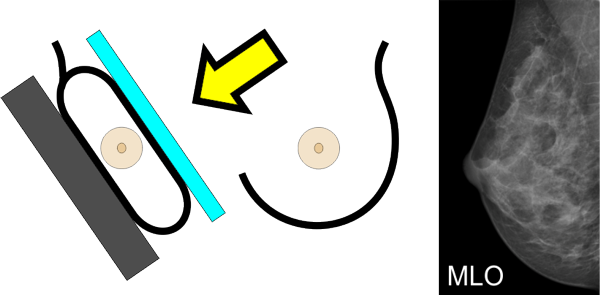

Von jeder Brust werden üblicherweise zwei Aufnahmen - jeweils von oben nach unten (cranio-caudale Aufnahme) und schräg von innen nach außen (medio-laterale oblique Aufnahme) - angefertigt. Die Brust wird dabei in eine Vorrichtung eingespannt und komprimiert:

können die Brustabschnitte in der Nähe der Achsel besser dargestellt werden.

Viele Frauen empfinden die Druckbelastung durch die Kompression als sehr unangenehm. Unsere Röntgentechnikerinnen sind deshalb speziell darauf geschult, möglichst schonend und behutsam vorzugehen.

Warum ist die Kompression notwendig?

Die Kompression beeinflusst die Qualität der Aufnahme. Je dünner die Brust ausgestrichen ist, desto besser und klarer wird das Bild, wie das Beispiel unten zeigt.

Eine gute Kompression ist für die Qualität der Aufnahme leider unumgänglich. Wir bemühen uns deshalb, möglichst behutsam und schonend vorzugehen.